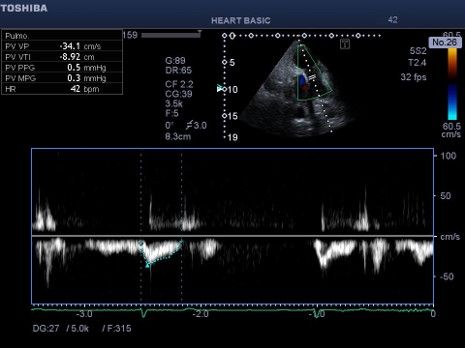

Εικόνα 3 .Παλμικό Doppler στο άκρα των γλωχίνων της τριγλώχινας . Το

σήμα της ανεπάρκειας έχει γραμμική ροή (ελεύθερη ανεπάρκεια). Η

μέγιστη ταχύτητα της ανεπάρκειας τριγλώχινας είναι 1,3 m/s που

αντιστοιχεί σε κλίση πίεσης 5 mmHg . Η δεξιά κοιλία δεν «γεννά πίεση» και

υπάρχει εξισορρόπηση πιέσεων μεταξύ πνευμονικής αρτηρίας, δεξιάς

κοιλίας και δεξιού κόλπου θυμίζοντας τη φυσιολογία της «επέμβασης

Fontan με συστηματική αριστερή κοιλία». Λόγω αύξησης των

πνευμονικών αντιστάσεων, δηλαδή λόγω αυξημένου μεταφορτίου της

δεξιάς κοιλίας, εμφανίζεται δεξιά καρδιακή ανεπάρκεια με χαμηλή

καρδιακή παρόχή με φυσιολογ ί α ομοιάζουσα με την « failing Fontan ».